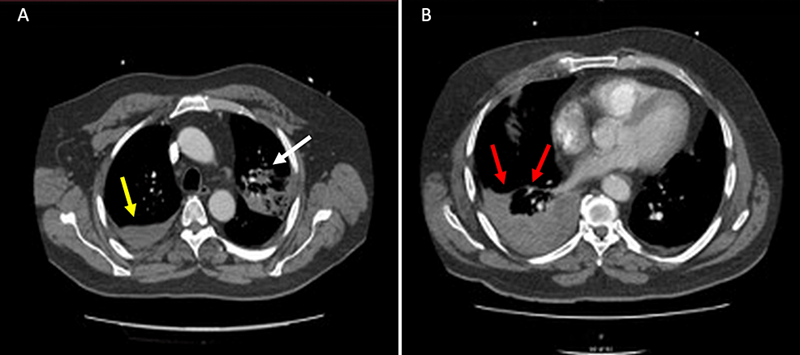

由于患者D-二聚体过高,怀疑

(图3

患者的